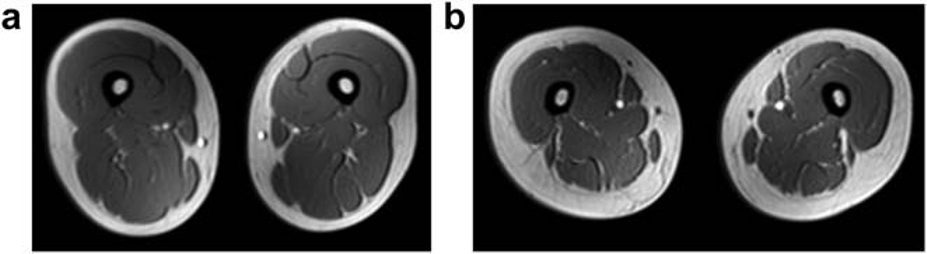

Figure: Representative magnetic resonance images of the femoral region in a female subject without non-alcoholic fatty liver disease (NAFLD) (a) and that in a female subject with NAFLD (b). The NAFLD subject had greater s.c. fat thickness, decreased muscle cross-sec-tion, and marbled muscles (steatosis) on the images.

The researchers found that of the male and female patients, one quarter of the members of each group had non-obese NAFLD. Surprisingly, these patients had lower skeletal muscle mass and muscle strength (pre-sarcopenia) compared with obese NAFLD patients. Although afflicted by fatty liver disease, there was only a modest increase in liver fat accumulation and insulin resistance (a precursor to diabetes and often associated with NAFLD) in non-obese NAFLD patients compared with obese NAFLD patients. This was further corroborated by the fact the visceral, or belly, fat was overall low in non-obese NAFLD patients. Interestingly, fat accumulation in muscles was more common among women. An integrated analysis of the data showed that liver fat accumulation in non-obese NAFLD was mainly dependent on visceral fat content, leptin (a hormone produced in visceral fat tissue and that induces inflammation), myostatin (a protein produced by skeletal muscle to suppress muscle regeneration) and HbA1c (a blood marker for how well the body manages blood sugar levels in the long term).